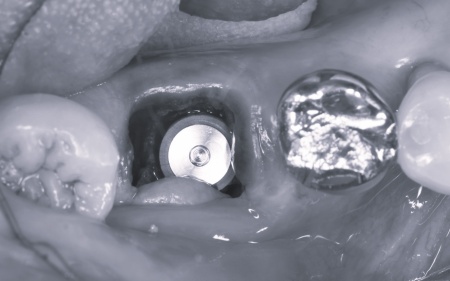

抜歯後、感染した組織を慎重に除去し同日にインプラント体を埋入しました。

骨とインプラントが結合するまでの期間は仮歯を装着し、噛み合わせや周囲組織の状態を確認しながら経過を観察しました。

骨とインプラントがしっかりと結合していることを確認したあと、型取りを行い被せ物を作製・装着しています。

またインプラント周囲の歯ぐきの安定性を高めるため、上あごの内側から歯肉を採取し大臼歯の周囲へ移植する角化歯肉移植を行いました。